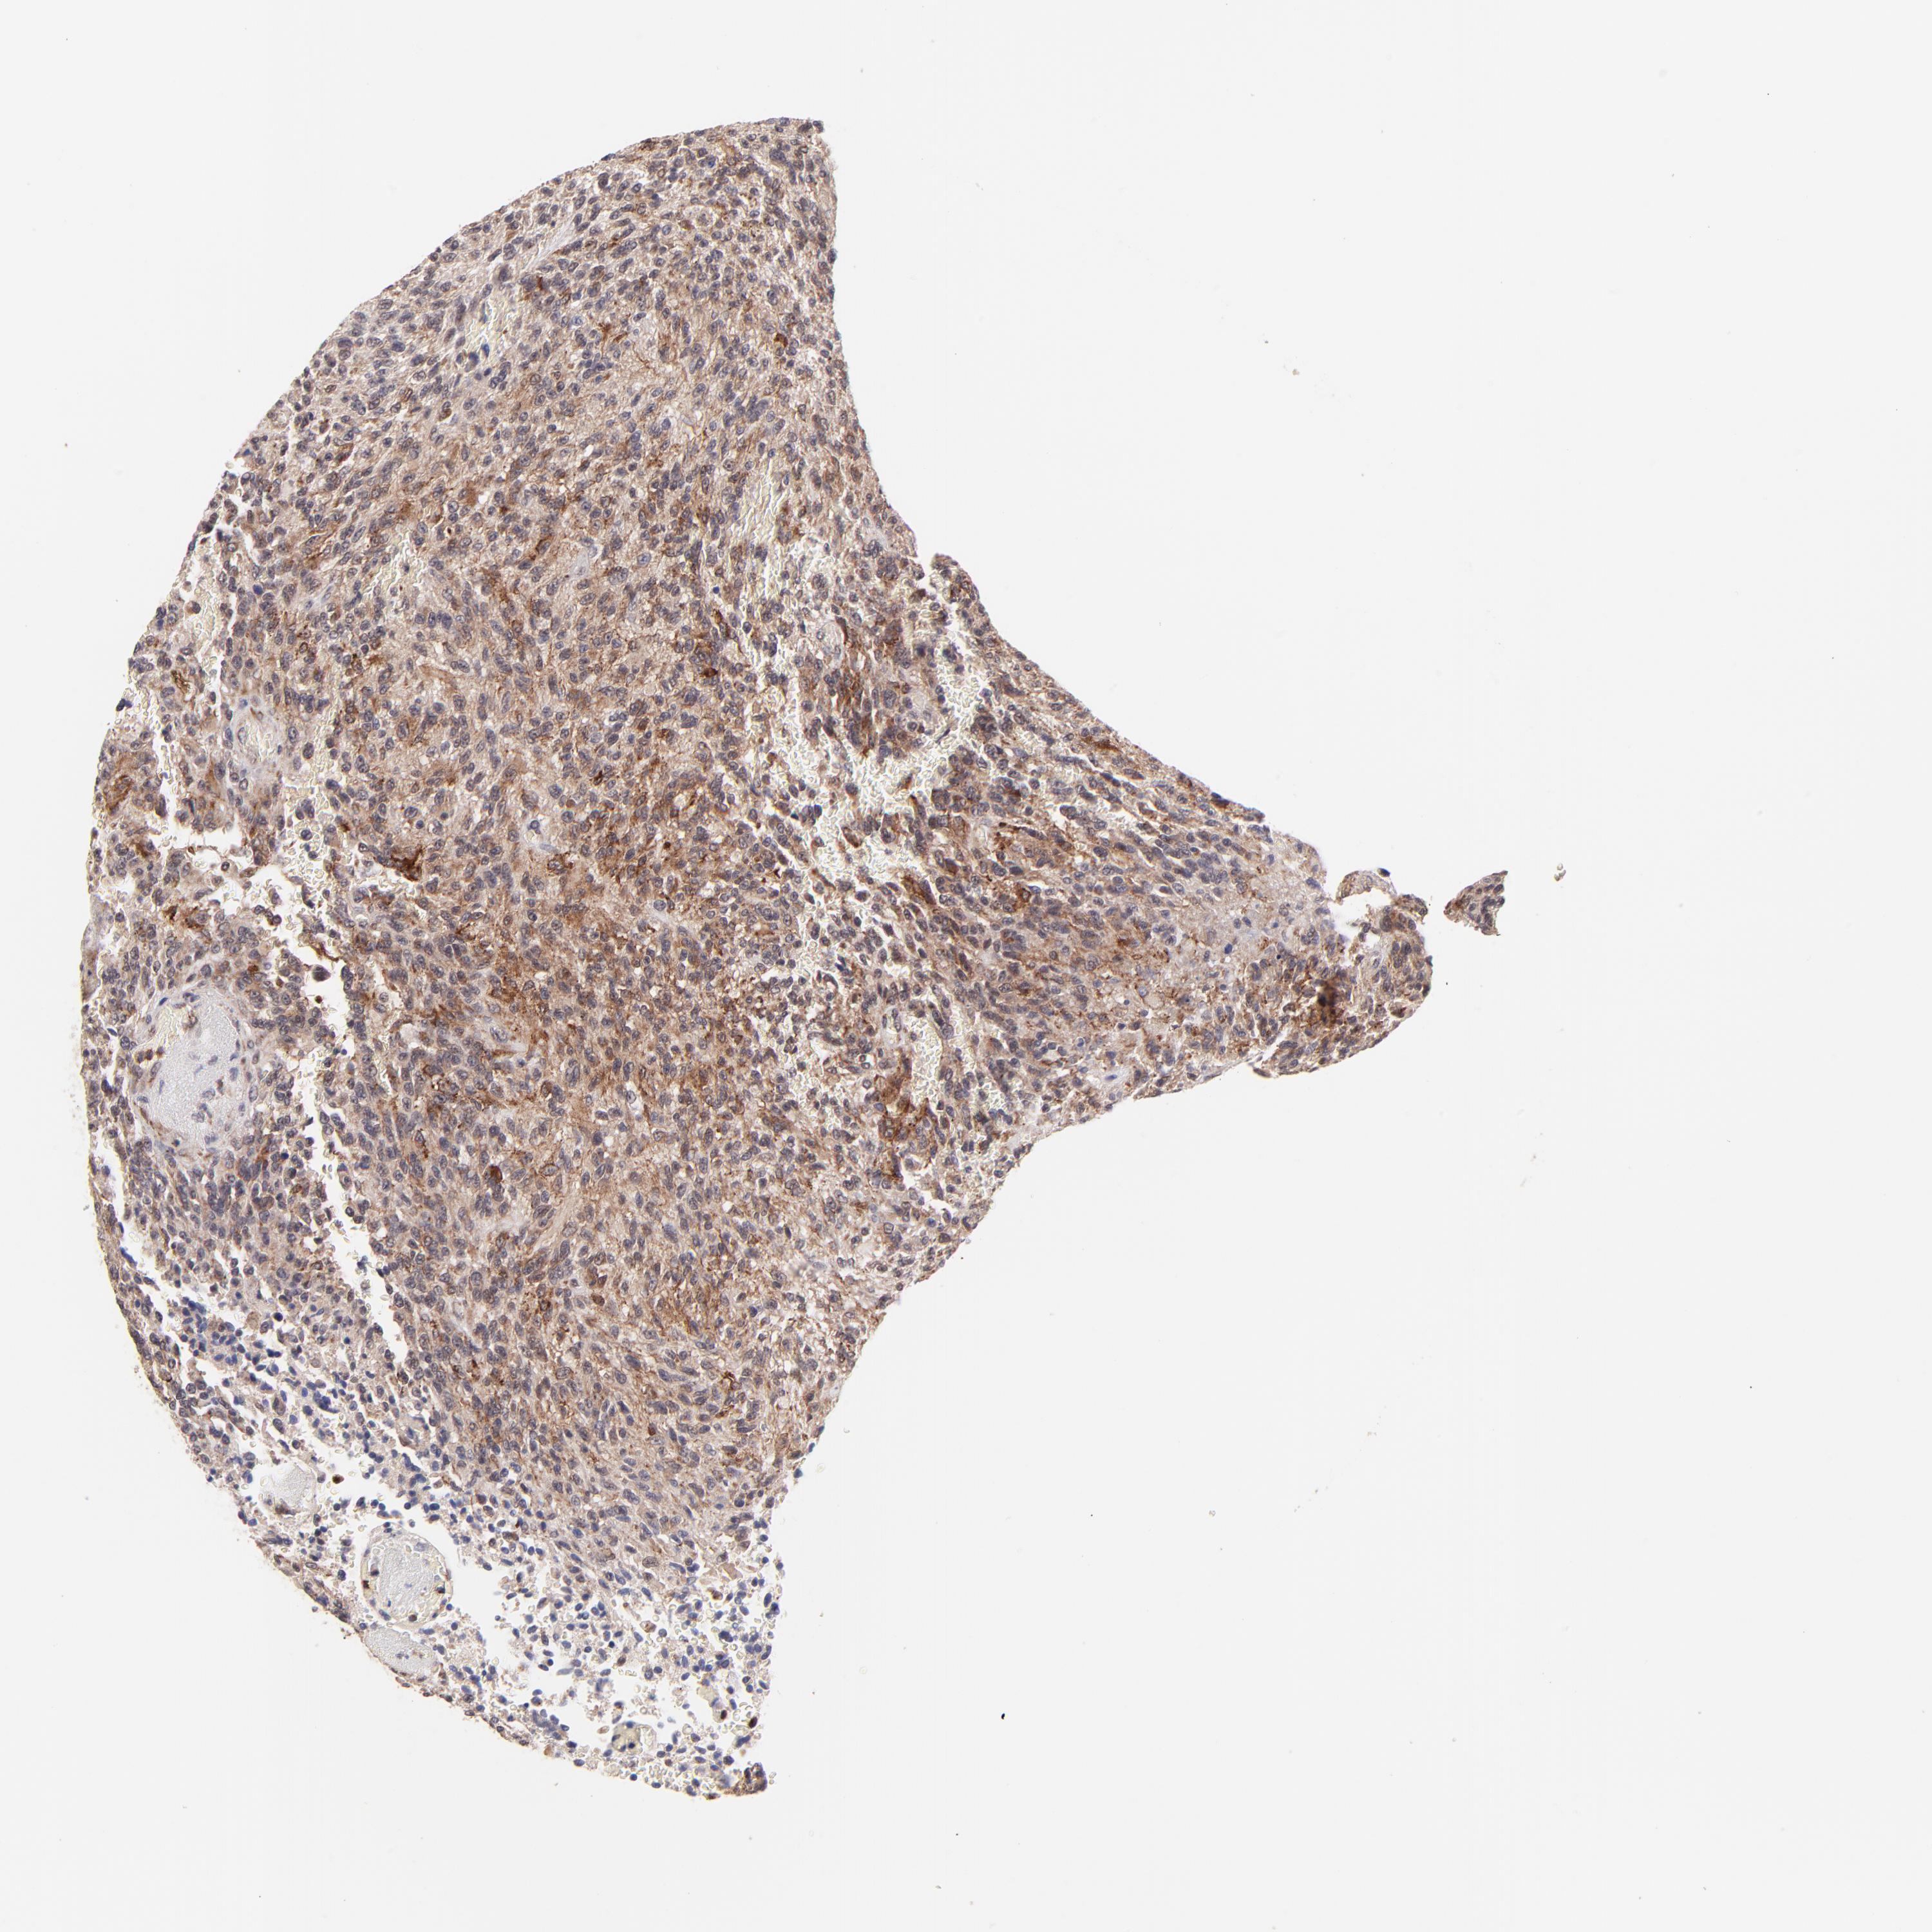

GLIOMA - Protein expressioni

A mouse-over function shows sample information and annotation data. Click on an image to view it in a full screen mode. Samples can be filtered based on level of antibody staining by selecting one or several of the following categories: high, medium, low and not detected. The assay and annotation is described here.

Note that samples used for immunohistochemistry by the Human Protein Atlas do not correspond to samples in the TCGA dataset.

Antibody stainingi

Antibody staining in the annotated cell types in the current human tissue is reported as not detected, low, medium, or high, based on conventional immunohistochemistry profiling in selected tissues. This score is based on the combination of the staining intensity and fraction of stained cells.

Each image is clickable and will lead to virtual microscopy that enables deeper exploration of all samples and also displays staining intensity scores, fraction scores and subcellular localization as well as patient and tissue information for each sample.

Antibody HPA003184

Antibody HPA003185

Staining

High

Medium

Low

Not detected

Intensity

Strong

Moderate

Weak

Negative

Quantity

>75%

75%-25%

<25%

None

Location

Nuclear

Cytoplasmic/membranous

Cytoplasmic/membranous,nuclear

Glioma, malignant, High grade

Glioma, malignant, Low grade

Glioma, malignant, NOS